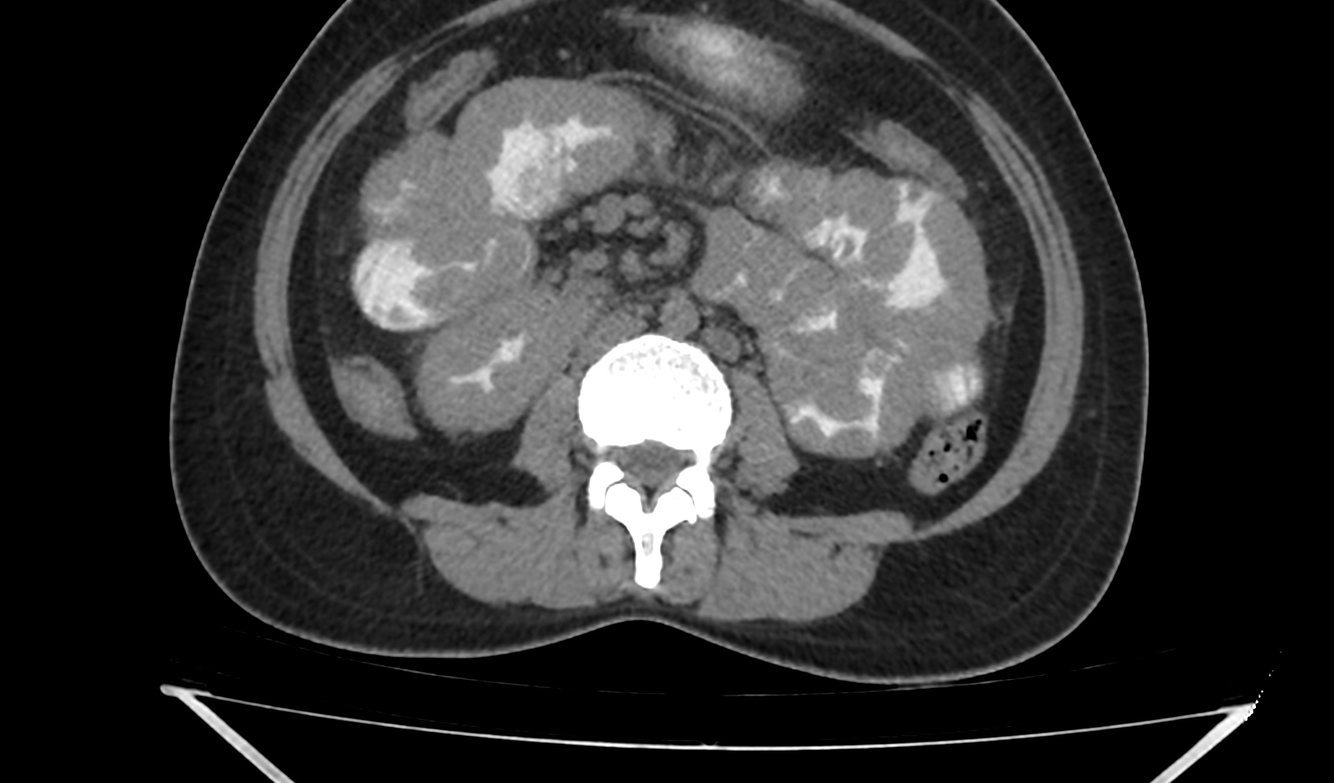

Case courtesy of Dr Prashant Mudgal, Radiopaedia.org, rID: 38098

The pancreas appears bulky and shows an ill-defined isodense hypoenhancing mass measuring approximately 4.3 x 2.0 cm. There is extensive polypoidal thickening of upper gastrointestinal tract wall, involving the pylorus of stomach, duodenum, jejunum and proximal ileum. The polyps measure 5 to 30 mm and causing luminal compromise. The proximal small bowel appears distended till distal ileum and there is an ileo-ileal intussusception noted in the distal ileum. The terminal ileum and large bowel appear collapsed.

There are few enlarged non-necrotic lymph nodes noted in the mesentery, the largest lymph node measures 1.3 x 0.8 cm in size. There is a well defined oval mass measuring approximately 6.0 x 4.5 cm noted in the right adnexa. The right ovary could not be separately visualized from the mass. The mass shows post contrast enhancement and central non-enhancing necrotic region within.

Extensive polypoidal mucosal thickening predominantly affecting the upper gastrointestinal tract with pancreatic and ovarian neoplasms are likely to represent gastrointestinal polyposis syndrome most likely Peutz Jeghers Syndrome.